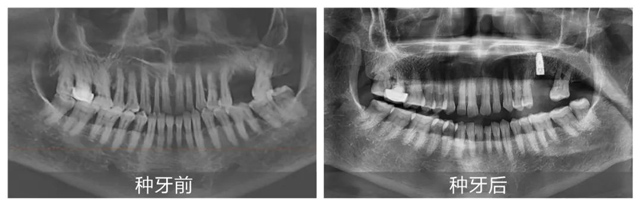

“在日常診療中,我們會(huì)依據(jù)患者的口腔情況一對(duì)一量身定制種植方案。而新橋口腔特別開設(shè)的數(shù)字化特檢科,可通過(guò)數(shù)字化CBCT影像、3D口掃等完成術(shù)前一站式檢查,規(guī)避后續(xù)治療中可能存在的風(fēng)險(xiǎn)與誤差。”李丹主任還表示:“定期開展的種植牙手術(shù)直播,通過(guò)實(shí)時(shí)轉(zhuǎn)播醫(yī)生的操作過(guò)程與顧客親身講述就診體驗(yàn),可以讓市民直觀感受到數(shù)字化種植的諸多優(yōu)點(diǎn)!”

在李丹主任細(xì)致講解的同時(shí),手術(shù)室已準(zhǔn)備就緒,上午10:32分,手術(shù)正式開始。從術(shù)前消毒到定量麻醉,從定點(diǎn)備洞到精準(zhǔn)植入,再到最后的嚴(yán)密縫合,黃杰醫(yī)生始終有條不紊地依序進(jìn)行。手術(shù)全程都由李丹主任與吳海燕主管同步配合講解,現(xiàn)場(chǎng)觀眾紛紛對(duì)黃杰醫(yī)生的精湛技術(shù)拍手稱贊。